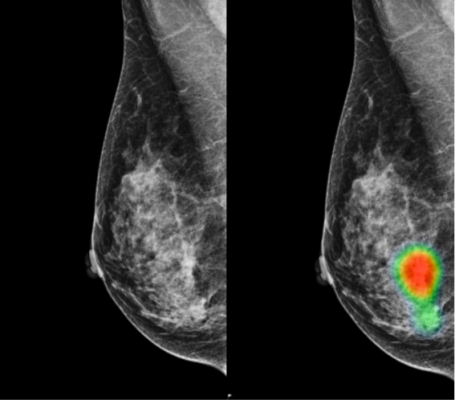

Ai Tool Improves Breast Cancer Detection On Mammography Imaging Technology News

Ai Tool Improves Breast Cancer Detection On Mammography Imaging Technology News from www.itnonline.com